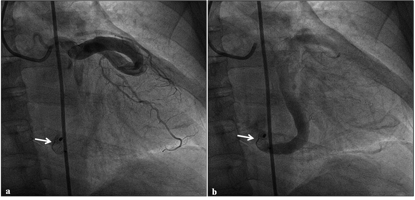

Figure 5. Check coronary angiogram at three months of follow-up. Right anterior oblique caudal projection revealed a device in situ (white arrow) and patent obtuse marginal branches, left atrial branches of the circumflex in early (A) and late phase (B) (click thumbnail to view larger image).

At 3 months of follow-up, coronary angiogram (Figures 5A and 5B, Video 3) revealed the complete closure of the fistula, with well-preserved obtuse marginal branches and left atrial branches of the left circumflex coronary artery. At 1-year follow-up, the patient is asymptomatic and doing well. We plan to continue anticoagulation indefinitely.